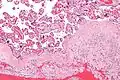

Micrograph of decidua in a lymph node. H&E stain.

The decidua has a histologically-distinct appearance, displaying large polygonal decidual cells in the stroma. These are enlarged endometrial stromal cells, which resemble epithelium (and are referred to as "epithelioid").